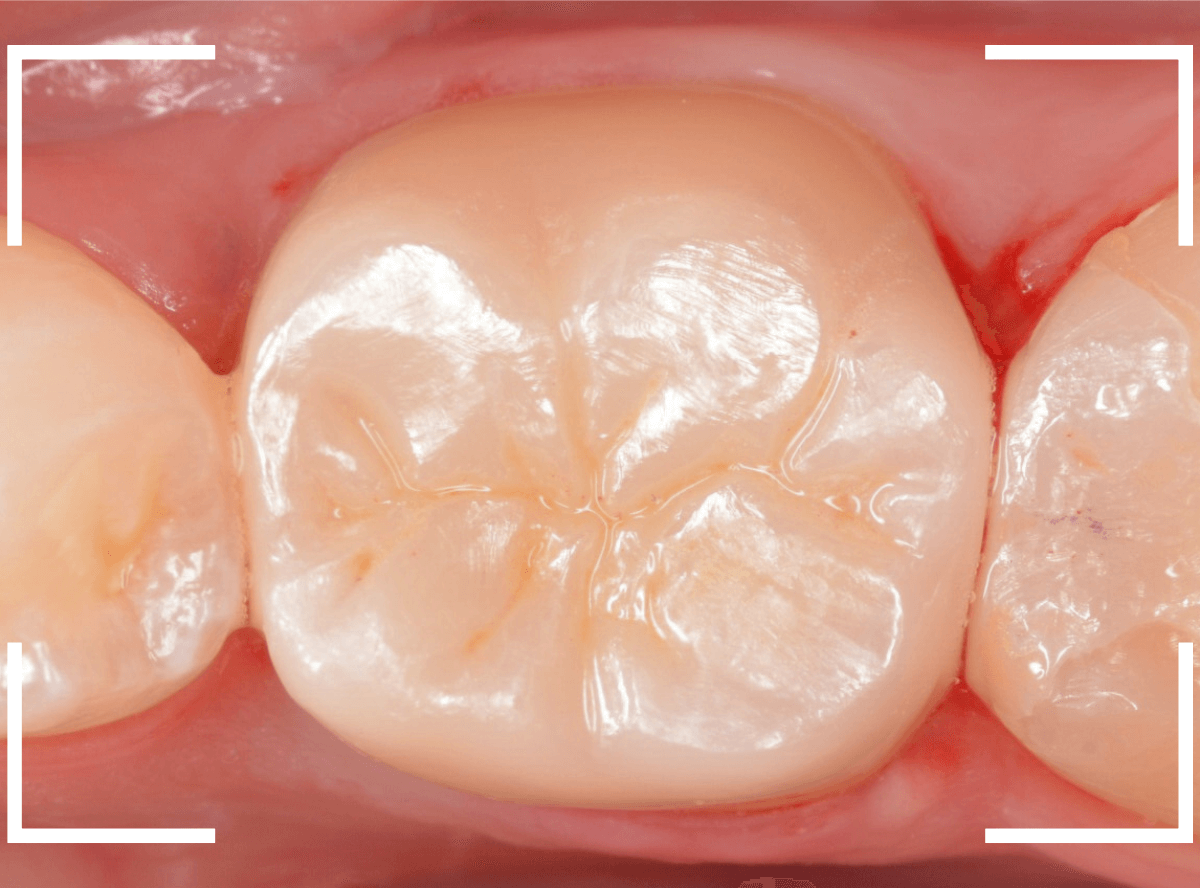

set後の写真です。

患者さんにも満足していただける仕上がりになりました。

治療前後の比較写真になります。